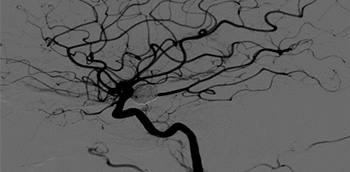

Aneurisma y MVC

El aneurisma cerebral es una protrusión en la pared de una arteria que condiciona la formación de un saco de paredes adelgazadas (“aneurisma sacular”). La zona de unión del saco con la pared arterial se denomina cuello y la relación entre el saco y el cuello va a...